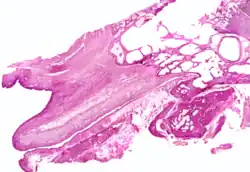

The cartilaginous part of the Eustachian tube is about 24 mm in length and is formed of a triangular plate of elastic fibrocartilage, the apex of which is attached to the margin of the medial end of the bony part of the tube, while its base lies directly under the mucous membrane of the nasal part of the pharynx, where it forms an elevation, the torus tubarius or cushion, behind the pharyngeal opening of the auditory tube.

The upper edge of the cartilage is curled upon itself, being bent laterally so as to present on transverse section the appearance of a hook; a groove or furrow is thus produced, which is open below and laterally, and this part of the canal is completed by fibrous membrane. The cartilage lies in a groove between the petrous part of the temporal bone and the great wing of the sphenoid; this groove ends opposite the middle of the medial pterygoid plate. The cartilaginous and bony portions of the tube are not in the same plane, the former inclining downward a little more than the latter. The diameter of the tube is not uniform throughout, being greatest at the pharyngeal opening, least at the junction of the bony and cartilaginous portions, and again increased toward the tympanic cavity; the narrowest part of the tube is termed the isthmus.

The position and relations of the pharyngeal opening are described with the nasal part of the pharynx. The mucous membrane of the tube is continuous in front with that of the nasal part of the pharynx, and behind with that of the tympanic cavity; it is covered with ciliated pseudostratified columnar epithelia and is thin in the osseous portion, while in the cartilaginous portion it contains many mucous glands and near the pharyngeal orifice a considerable amount of adenoid tissue, which has been named by Gerlach the tube tonsil.